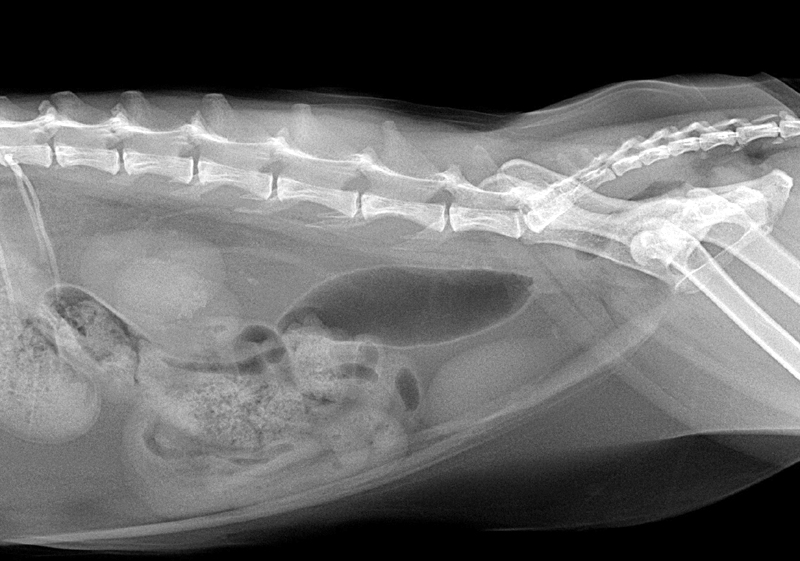

From 2010vets.blogspot.com

Be Kind To Pets, Vet case studies, Photography tips, Travel Stories How Can You Tell If A Cat Has Kidney Stones Cats almost always develop calcium oxalate stones that. Learn from our vet's explanation what the causes, signs, treatment, and more. Signs of kidney stones in cats. Your cat may or may not have obvious signs of kidney stones. The signs and symptoms of kidney stones could include: Symptoms of kidney stones in cats. Kidney stones (which are rare in cats). How Can You Tell If A Cat Has Kidney Stones.